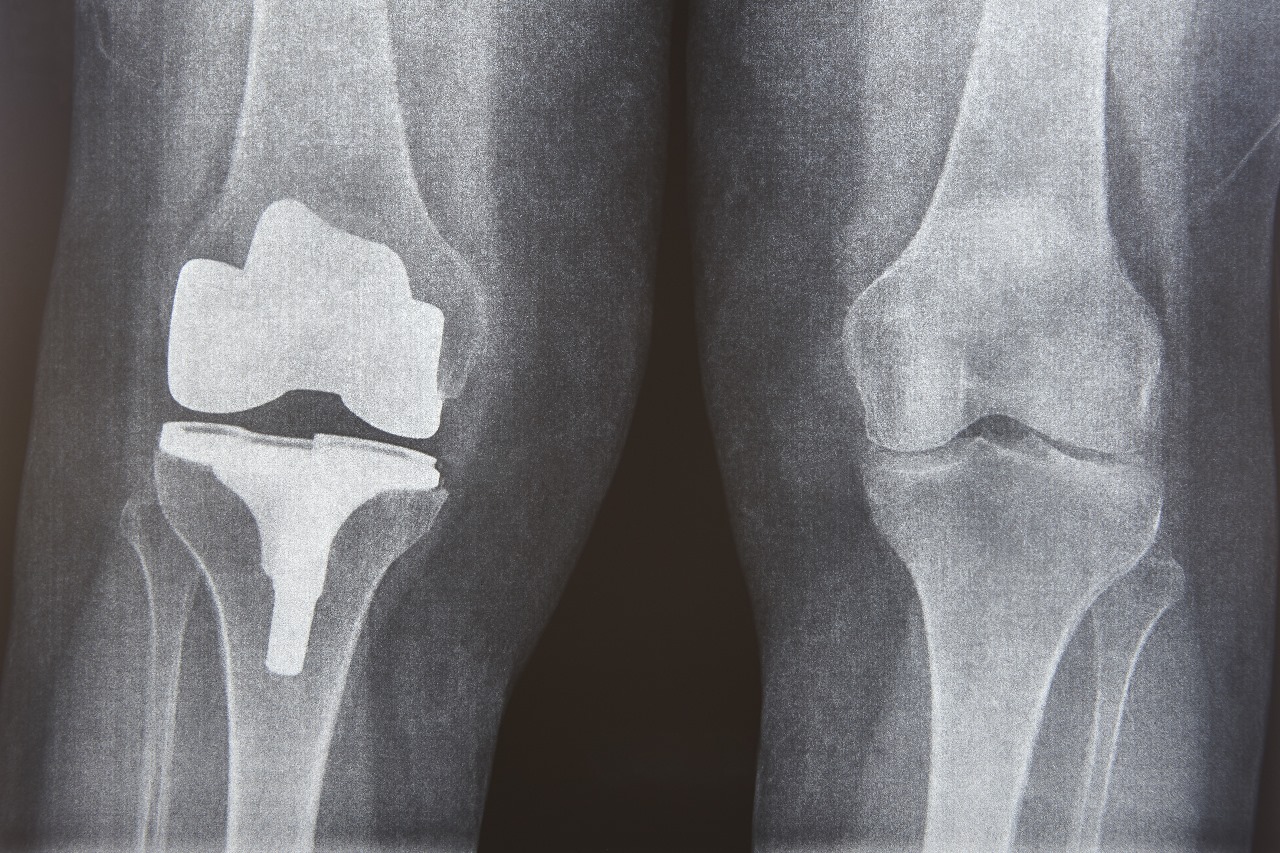

The surgical procedures performed in our Hip Replacement department at Niramaya prioritize precision and innovation. Our orthopedic surgeons utilize advanced prosthetic implants and cutting-edge surgical techniques, including minimally invasive approaches when appropriate. This focus on modern technology ensures not only optimal surgical outcomes but also quicker recovery times and improved overall joint functionality for our patients.